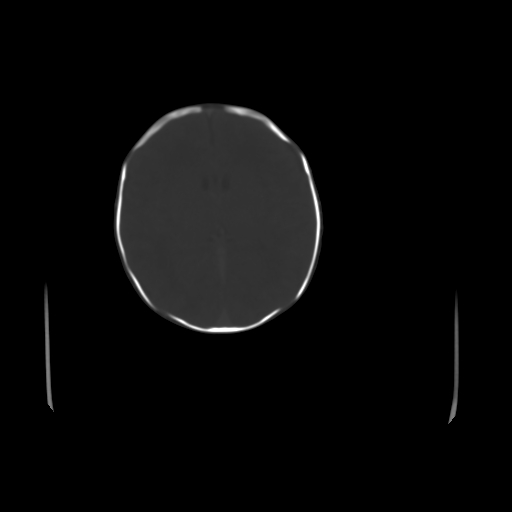

男,12天,自然分娩,其母发现右顶部头皮包块逐渐增大。

右顶部头皮血肿

右顶部头颅血肿(骨膜下血肿)

右顶骨呈膨胀性改变,骨纤维结构不良?